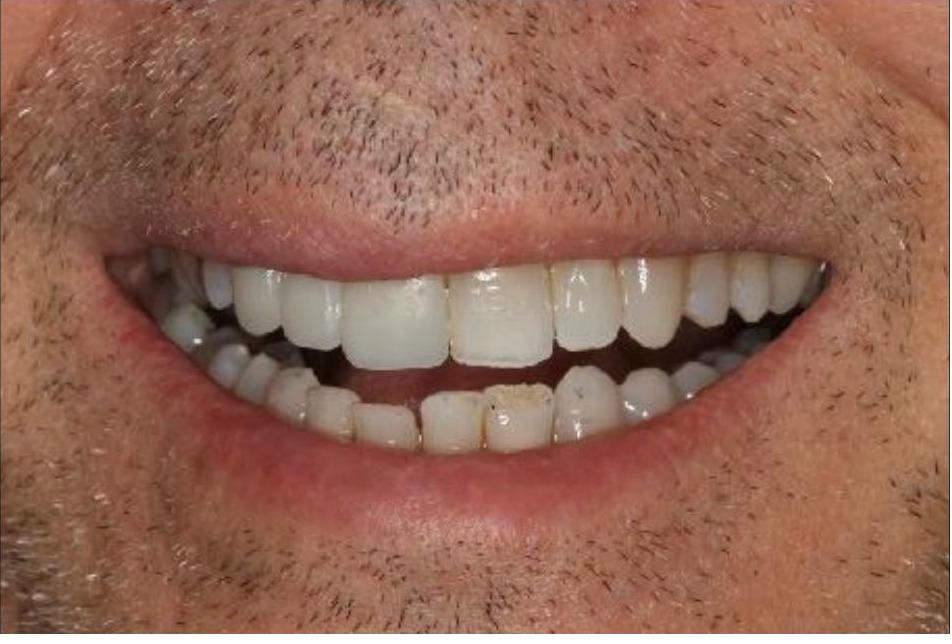

This patient had significant wear and chipping of his teeth. To restore his dental esthetics and function, following orthodontic therapy I fabricated crowns for his front teeth to restore the proper length, contour, and esthetics. He was thrilled with the result of our interdisciplinary care.

This patient had numerous cavities and missing teeth and wanted to improve his dental health and esthetics. Working closely with a periodontist who placed implants in the sites of the missing teeth along with my laboratory technician, I fabricated a combination of crowns on his upper natural teeth and implant crowns to restore his dental health, bite, function and esthetics. He was extremely happy with the result!